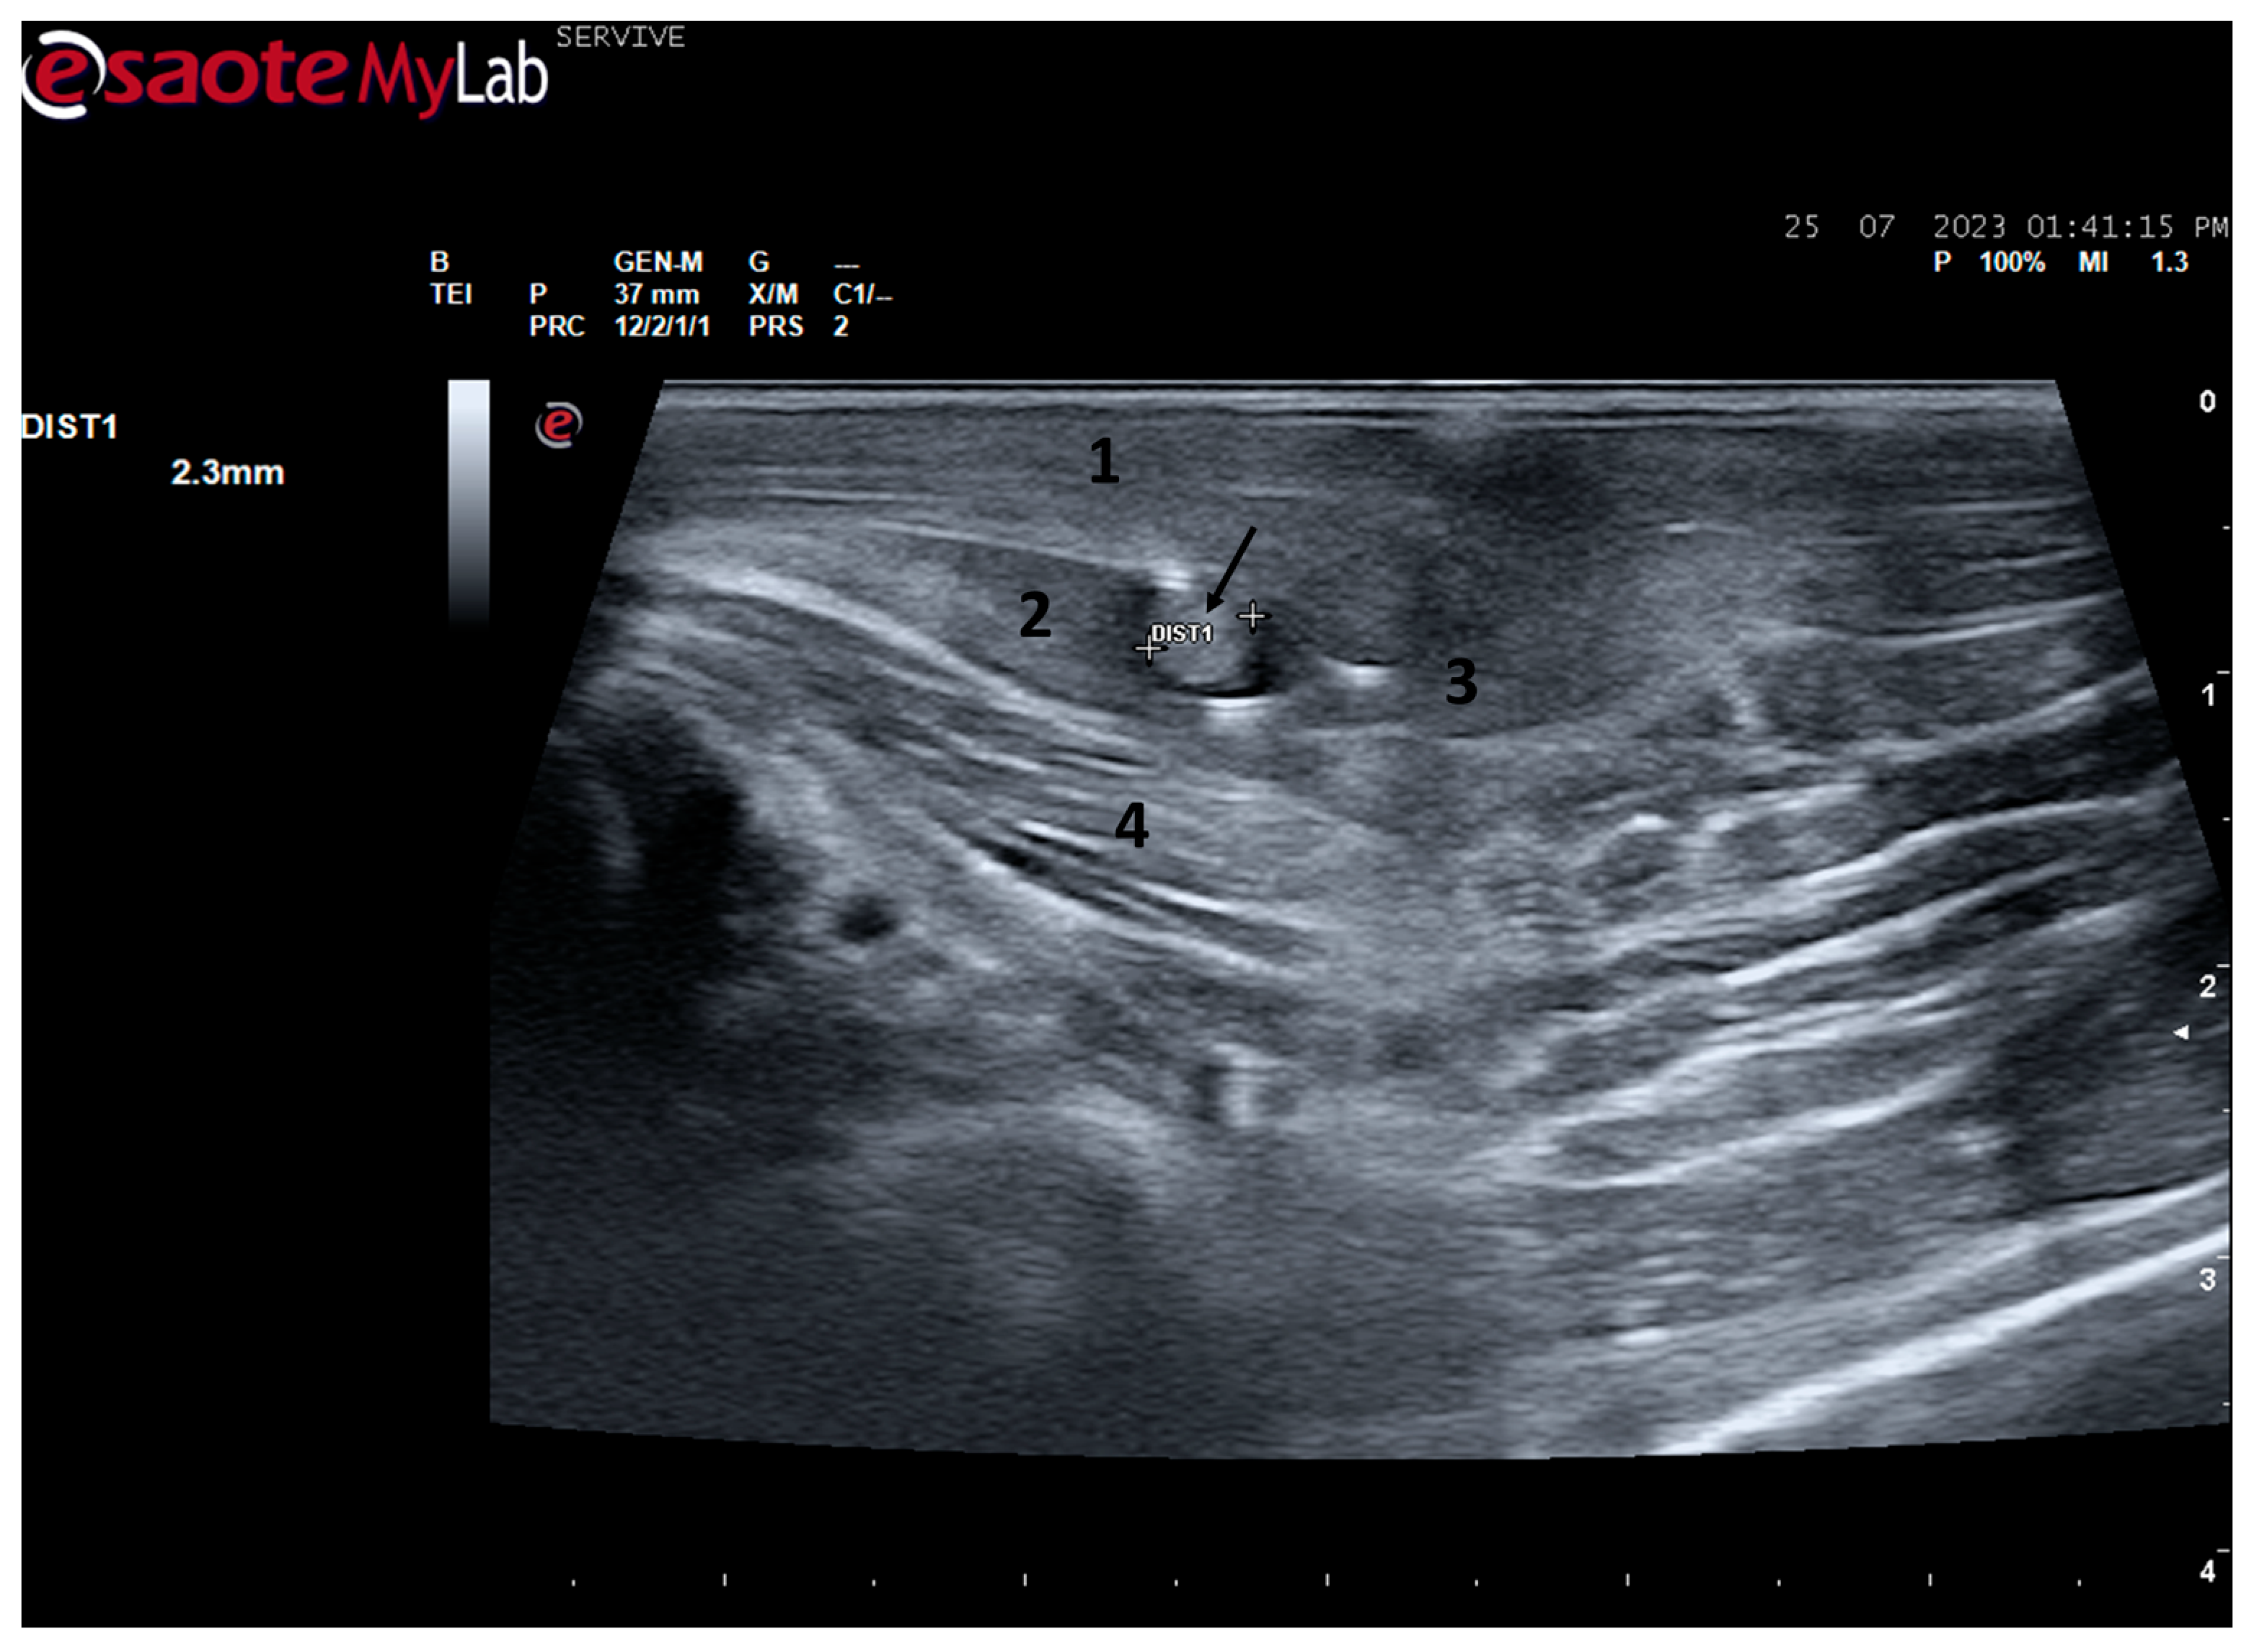

The sciatic nerve was easily identified mid-thigh medially to the biceps femoris muscle and caudal to the femur and vastus lateralis muscle, allowing these muscles to be used as reference points for quick identification even for less experienced ultrasonographers. Monitoring the nerve in a proximal direction makes it possible to identify its passage between the greater trochanter of the femur and the ischial tuberosity, and these bony projections can be used as a reference point for its location. More proximally is its emergence from the greater sciatic foramen. At this level, the nerve may be more difficult to identify due to its curvature and also due to its proximity to the caudal gluteal artery and vein, but the use of a color-flow Doppler may clear up any doubts. Confusion with the sacred loin trunk in this region will be more unlikely since it is at greater depth. The sciatic nerve can also be easily tracked distally to the point where it branches proximally to the stifle. As the nerve progresses, an increase in echogenicity seems to be observed, a phenomenon described in other species [16], and which is probably related to an increase in the connective tissue within the nerve. It is important to remember that this increase in the amount of connective tissue is also related to an increased likelihood of compression or stretching injuries, making it harder to observe the nerve and apply local anesthetic blocks [26]. The mean diameter of the sciatic nerve measured mid-thigh and just before its branching site is identical to that indicated in other species, such as dogs of similar size. Its ultrasound appearance is similar to that described in other species, such as humans [27], dogs [14,15], or cats [16], appearing as a hypoechogenic tubular structure covered by a hyperechogenic envelope corresponding to the epineurium, an aspect that allows its easy differentiation from soft tissues and bones in the vicinity. Before its branching site, the sciatic nerve diameter was also measured in a cross-section, rotating the probe 45 degrees from the position that allows for obtaining the longitudinal image (Figure 8). Obtaining an image in this plane proved to be more complex and made it difficult to establish anatomical relationships with neighboring structures and with the ramifications of the sciatic nerve. On the other hand, the ultrasound image reveals characteristics identical to those obtained in the regular plane, in addition to the measured diameter being the same as that obtained with the previous technique. Therefore, it was decided not to use the transverse plane for this ultrasound characterization in any of the considered nerves.

Figure 8.

Ultrasound image of the left sciatic nerve before its branching site, cross section (black arrow). In this plane, the nerve appears as an echogenic tubular structure surrounded by the musculature of the region. (1) Biceps femoris muscle; (2) vastus lateralis muscle; (3) Semitendinosus muscle (4) adductor muscles. DIST1 represents the measurement of the diameter of the sciatic nerve before its branching site.